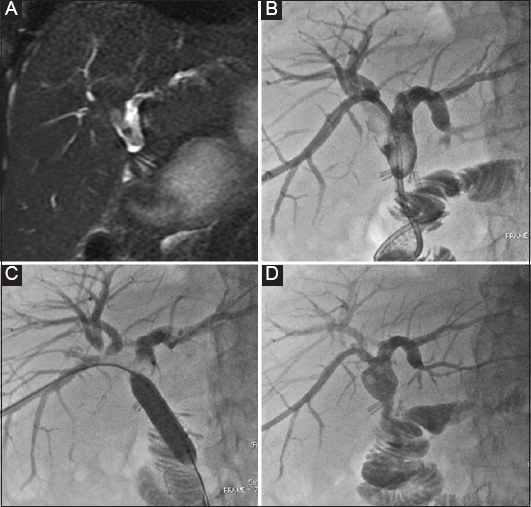

thumblarge

Figure 3 A 48-year-old female patient with benign stenosis post biliodigestive anastomosis. (A) Initial drainage because of multiple small stones. (B) Cholangioscopic inspection to assess the presence of stones that were not visible in the cholangiogram. (C) Three months later, a new cholangiogram revealed the presence of a large stone (arrow). (D) The stone was retrieved with an extraction balloon. Presence of a “buddy-wire” to maintain access to the biliary tree

The success rates of balloon angioplasty for intrahepatic bile duct stone reach as high as 95.23% [11,41] of cases, with an average procedure duration of 65.8±5.3 min. On average, patients stayed in the hospital for 10.7±1.5 days. No instances of pancreatitis, gut issues, or perforations in the biliary duct were reported. Over a follow-up period of 2 years, there were no signs of reflux cholangitis or stone recurrence [11]. Comparing percutaneous transhepatic papillary balloon dilation (PTPBD) with ERCP, the PTPBD technique had a success rate of 99% compared to 98% for the ERCP technique (relative risk 1.02, 95%CI 0.91-1.08; P=0.12). Complication rates were lower for PTPBD at 4% (13 of 360) versus ERCP at 8% (13 out of 171) (relative risk 0.27, 95%CI 0.12-0.61; P<0.001). The PTPBD procedure took more time under fluoroscopy and resulted in greater radiation exposure, with an average difference of 28.7 min (95%CI 22.2-35.2) and 384.3 mGy (95%CI 296.5-472). When matched groups were compared using a propensity score analysis, PTPBD displayed a marginally better success rate and notably fewer complications [42] (Table 1).